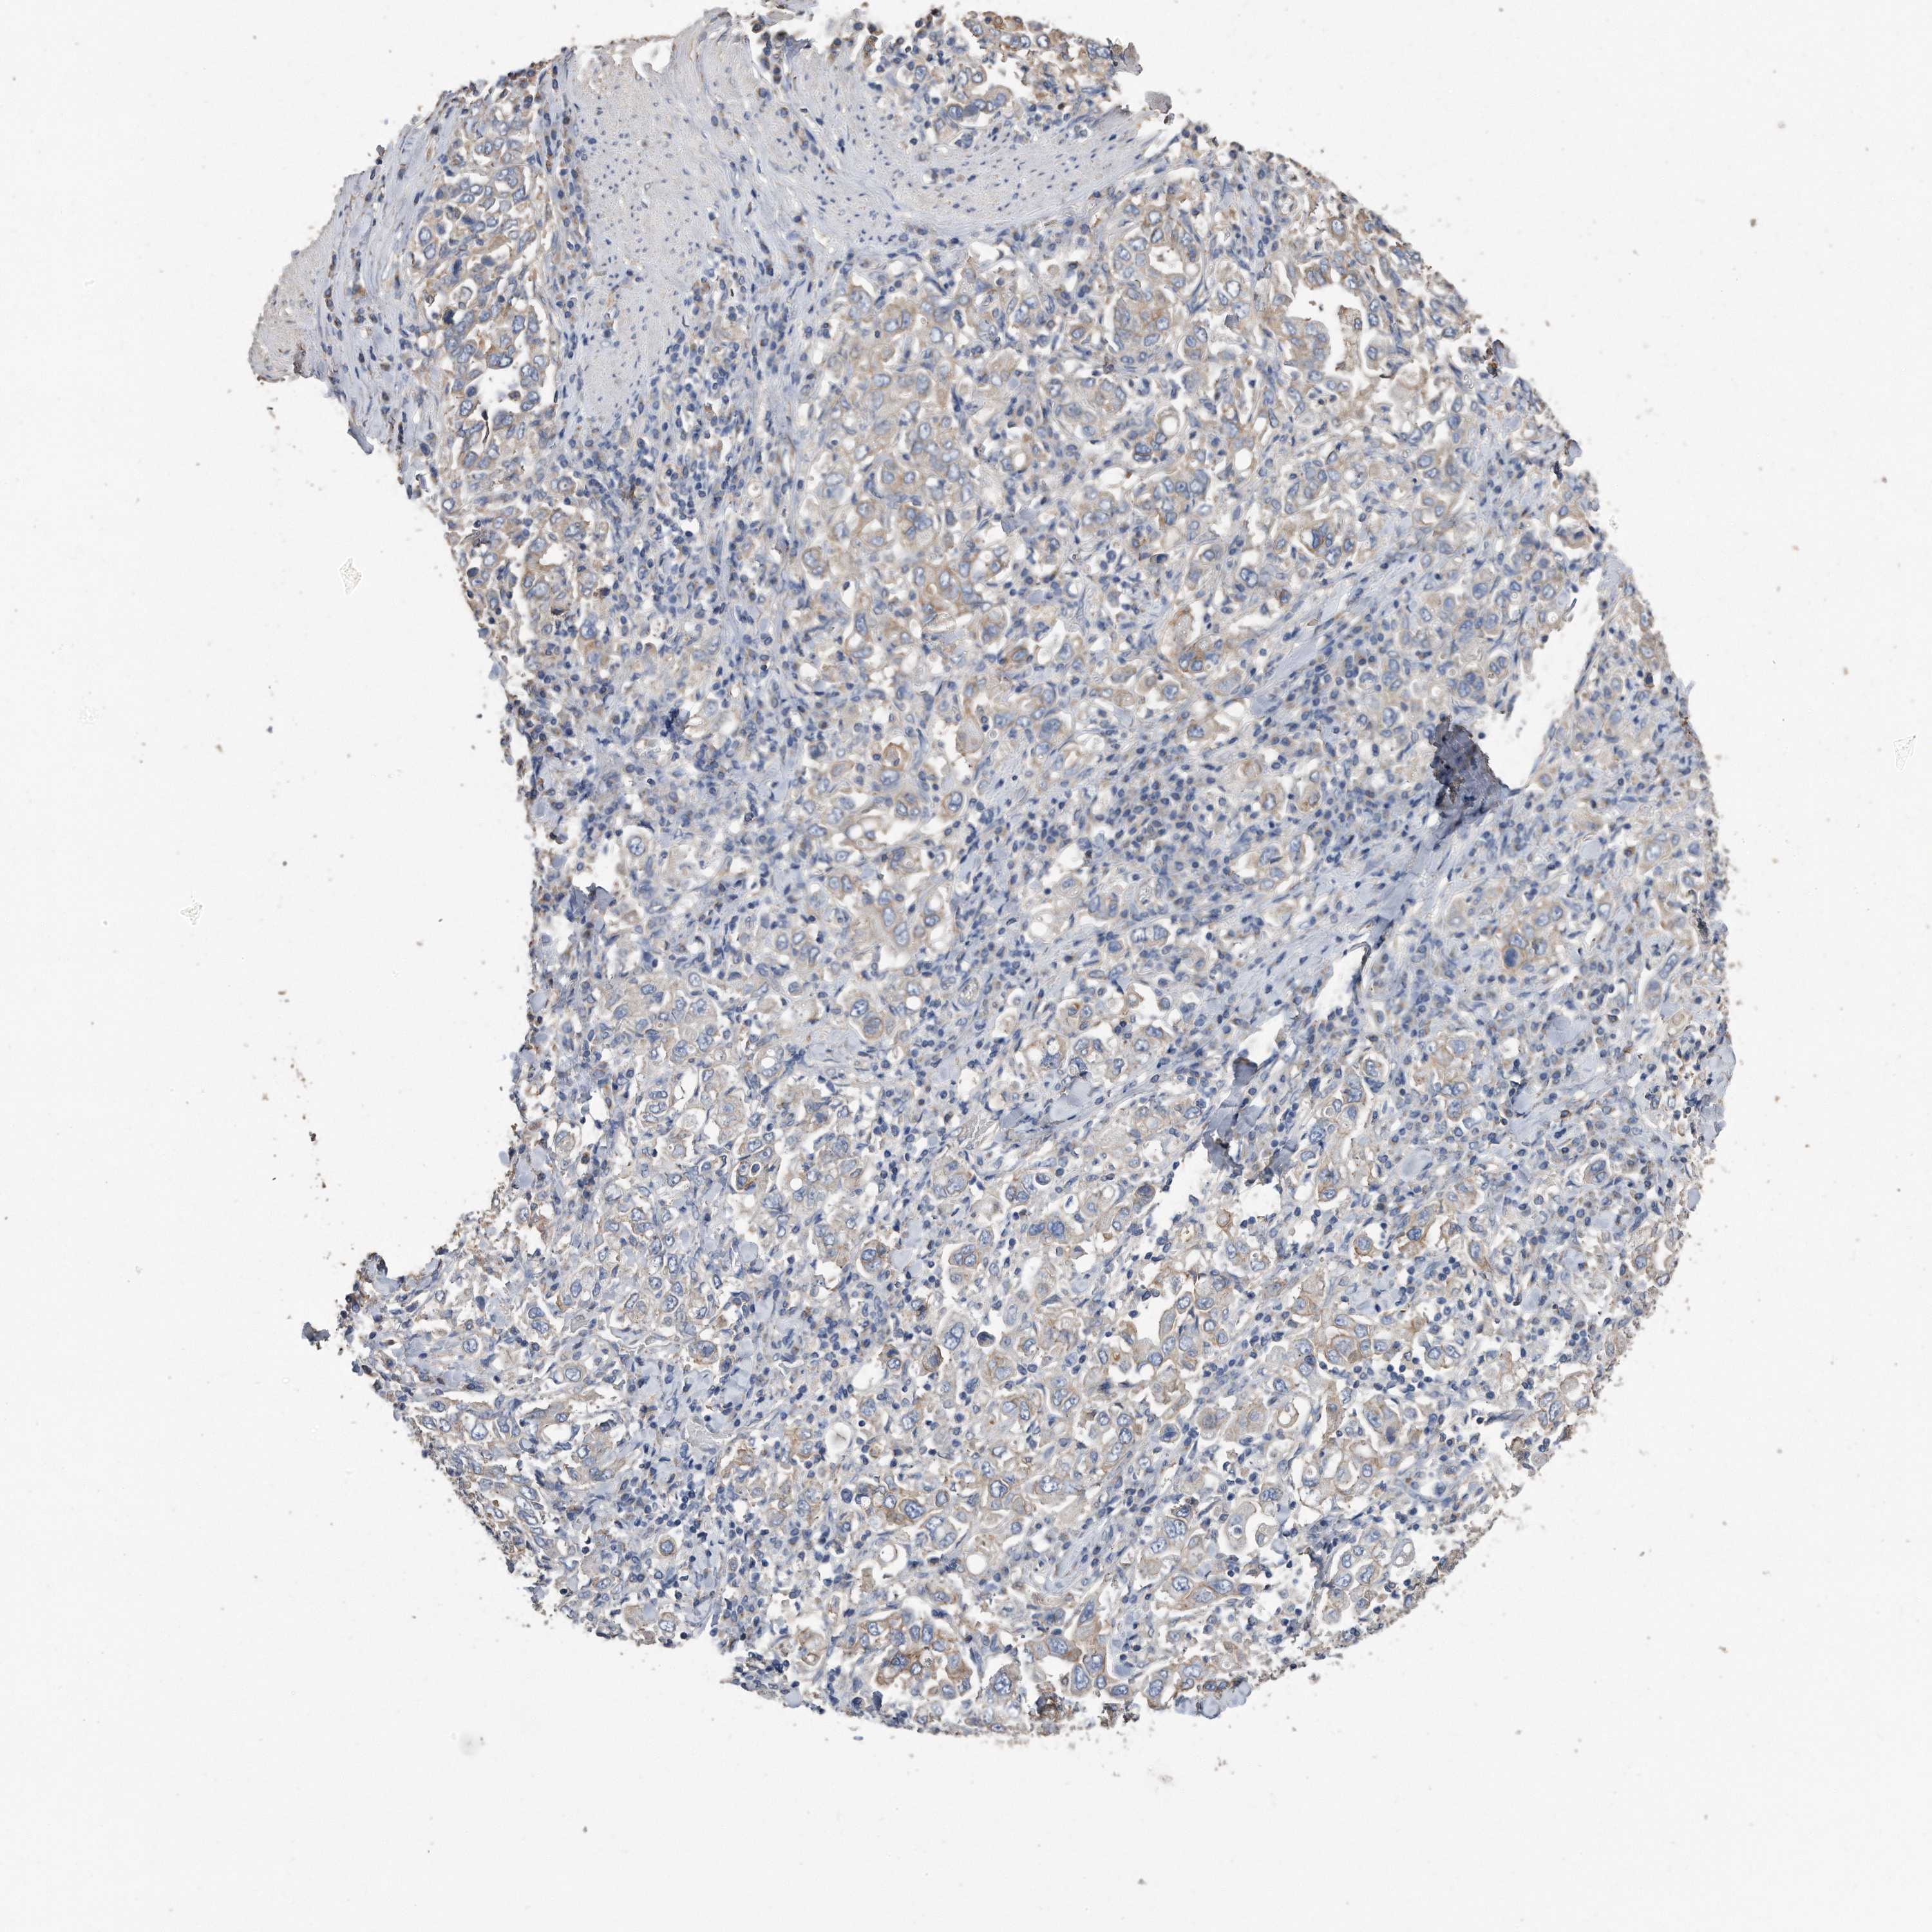

STOMACH CANCER - Protein expressioni

A mouse-over function shows sample information and annotation data. Click on an image to view it in a full screen mode. Samples can be filtered based on level of antibody staining by selecting one or several of the following categories: high, medium, low and not detected. The assay and annotation is described here.

Note that samples used for immunohistochemistry by the Human Protein Atlas do not correspond to samples in the TCGA dataset.

Antibody stainingi

Antibody staining in the annotated cell types in the current human tissue is reported as not detected, low, medium, or high, based on conventional immunohistochemistry profiling in selected tissues. This score is based on the combination of the staining intensity and fraction of stained cells.

Each image is clickable and will lead to virtual microscopy that enables deeper exploration of all samples and also displays staining intensity scores, fraction scores and subcellular localization as well as patient and tissue information for each sample.

Antibody HPA010978

Antibody HPA010979

Antibody CAB025637

Staining

High

Medium

Low

Not detected

Intensity

Strong

Moderate

Weak

Negative

Quantity

>75%

75%-25%

<25%

None

Location

Nuclear

Cytoplasmic/membranous

Cytoplasmic/membranous,nuclear

Adenocarcinoma, NOS

Adenocarcinoma, High grade